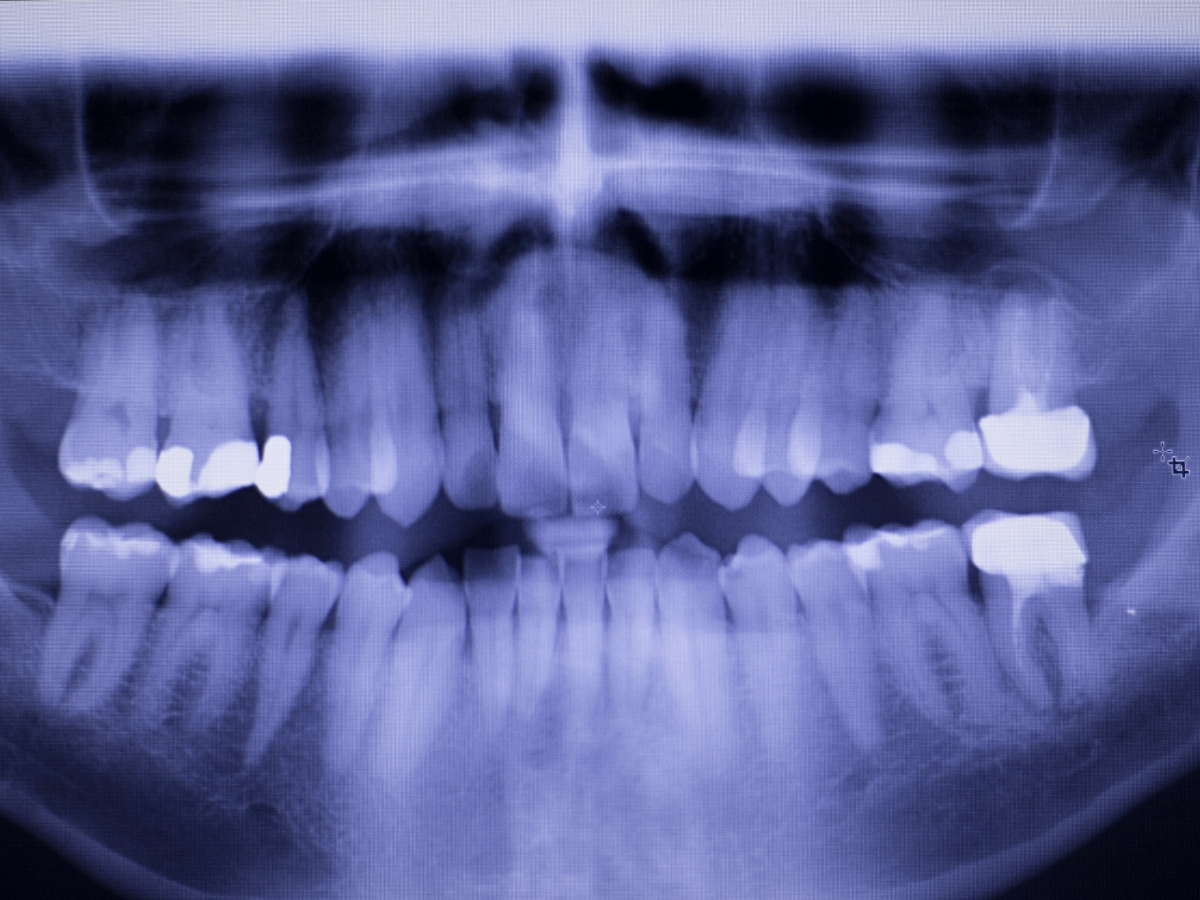

At Happy Smiles Dentist, we understand how important it is to have healthy teeth and a gorgeous smile. If you have a hole or cavity in your teeth or feel like there could be, it is vital to see your dentist prevent further decay and damage. Our dentists are highly experienced in Composite Resin Filling, Porcelain Filling and Amalgam Fillings. If you feel concerned and think you may need a filling, feel free to contact the Happy Smiles Dentist team on 02 9477 1803.

For various reasons, you may feel as though you require a filling. If you are based in Hornsby & Surrounding Areas and are experiencing pain, sensitivity or can feel a hole in your tooth, consider booking in for a dentist filling. You may have concerns when getting a filling. Here at Happy Smiles Dentists, we put your concerns at ease by having the most highly trained and experienced dentists and the best equipment and filling materials on the market.